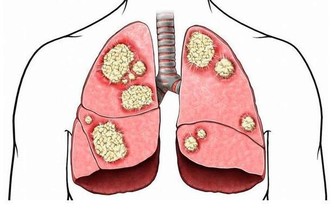

4、桑椹具有免疫促進作用,可以防癌抗癌;